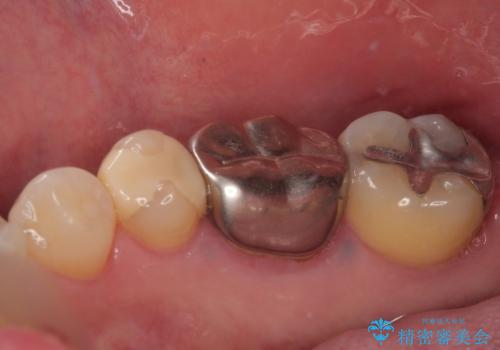

- 適合の良くない銀の詰め物が入っており、白い詰め物へのやり替えをご希望された患者様です。

メタルインレーを除去したところ、虫歯ができていたため取り除いたうえでハイブリッドインレー修復を行いました。

インレーセット時には唾液の侵入を防ぐためにラバーダム防湿を行っています。